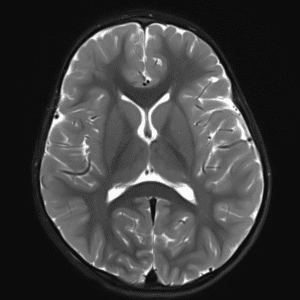

Case #30

Arachnoid cyst